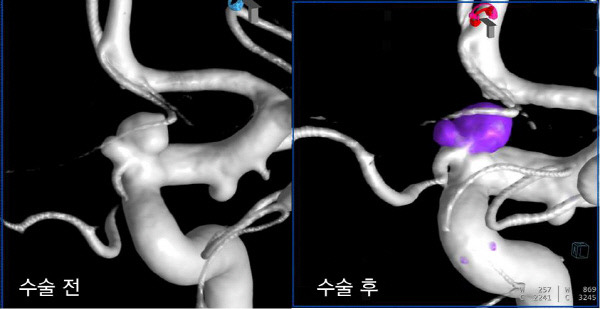

코일색전술은 뇌를 열지 않고 혈관 내에서 동맥류를 치료하는 방법으로, 대퇴동맥을 통해 삽입한 카테터를 이용하여 동맥류 내부에 백금 코일을 채워 혈류를 차단하는 시술입니다. 이를 통해 동맥류의 파열을 방지할 수 있습니다.

- 코일 삽입: 카테터를 통해 백금 코일을 동맥류 내부에 채워 넣습니다.

- 마무리: 코일 삽입이 완료되면 카테터를 제거하고 삽입 부위를 지혈합니다.